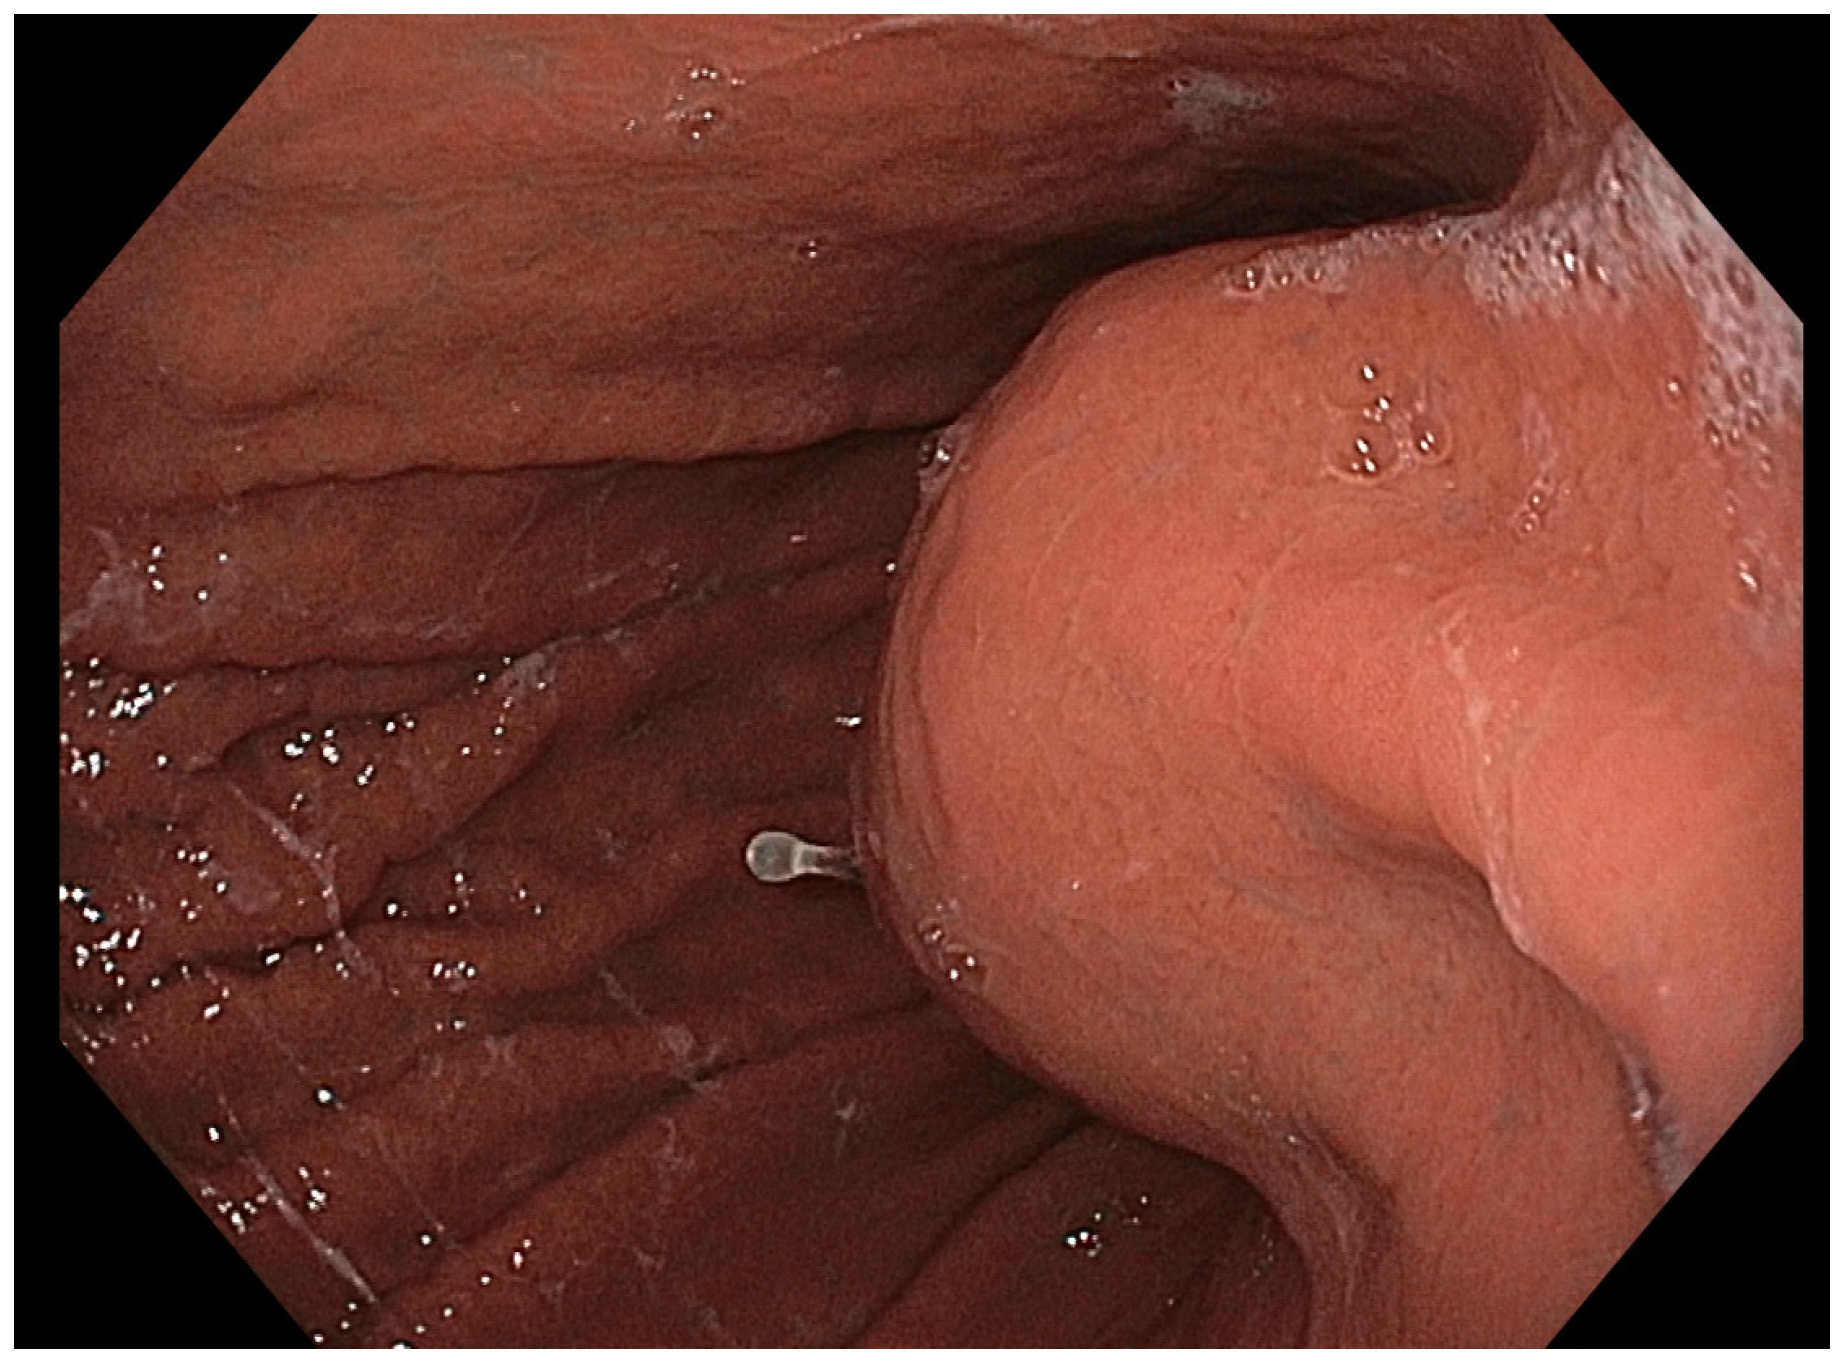

A 61-year-old woman in otherwise good health was admitted to our institute reporting severe abdominal pain. The patient underwent cholecystectomy many years ago. He had no known family history of gastrointestinal, hepatic, biliary, or pancreatic disease. Laboratory tests were normal at admission, and even neoplastic markers were negative. A contrast-enhanced computed tomography (CE-CT) scan showed a large (37 × 34 mm) lesion at the gastric body, next to the pancreatic body, suspected to originate from the gastric wall. Specifically, the CT scan findings of the lesion showed regular margins with a small central necrotic area and post-contrast enhancement. A direct endoscopic view showed a large bulging into the gastric lumen with a normal overlying mucosa (Figure 1).

Figure 1.

Endoscopic image demonstrating a well-circumscribed, smooth bulge in the gastric wall with intact and normal-appearing mucosa, consistent with a gastric subepithelial lesion.